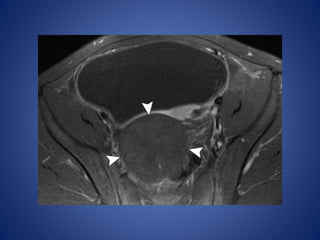

Testicular adrenal rest tumors in adrenogenital syndrome are

very common in boys with CAH.

These tumors are small, generally multiple, and often bilateral.

The involved testis may be enlarged, but its contour is not

distorted. The masses are eccentric and commonly surround the

mediastinum testis.

Their appearance at US is variable and depends on size.

Smaller lesions (<2 cm) appear hypoechoic compared with the adjacent

testicle, whereas larger lesions appear hyperechoic with posterior acoustic

shadowing.

At color Doppler imaging, vessels may be seen coursing through the lesion

without being deviated by it.